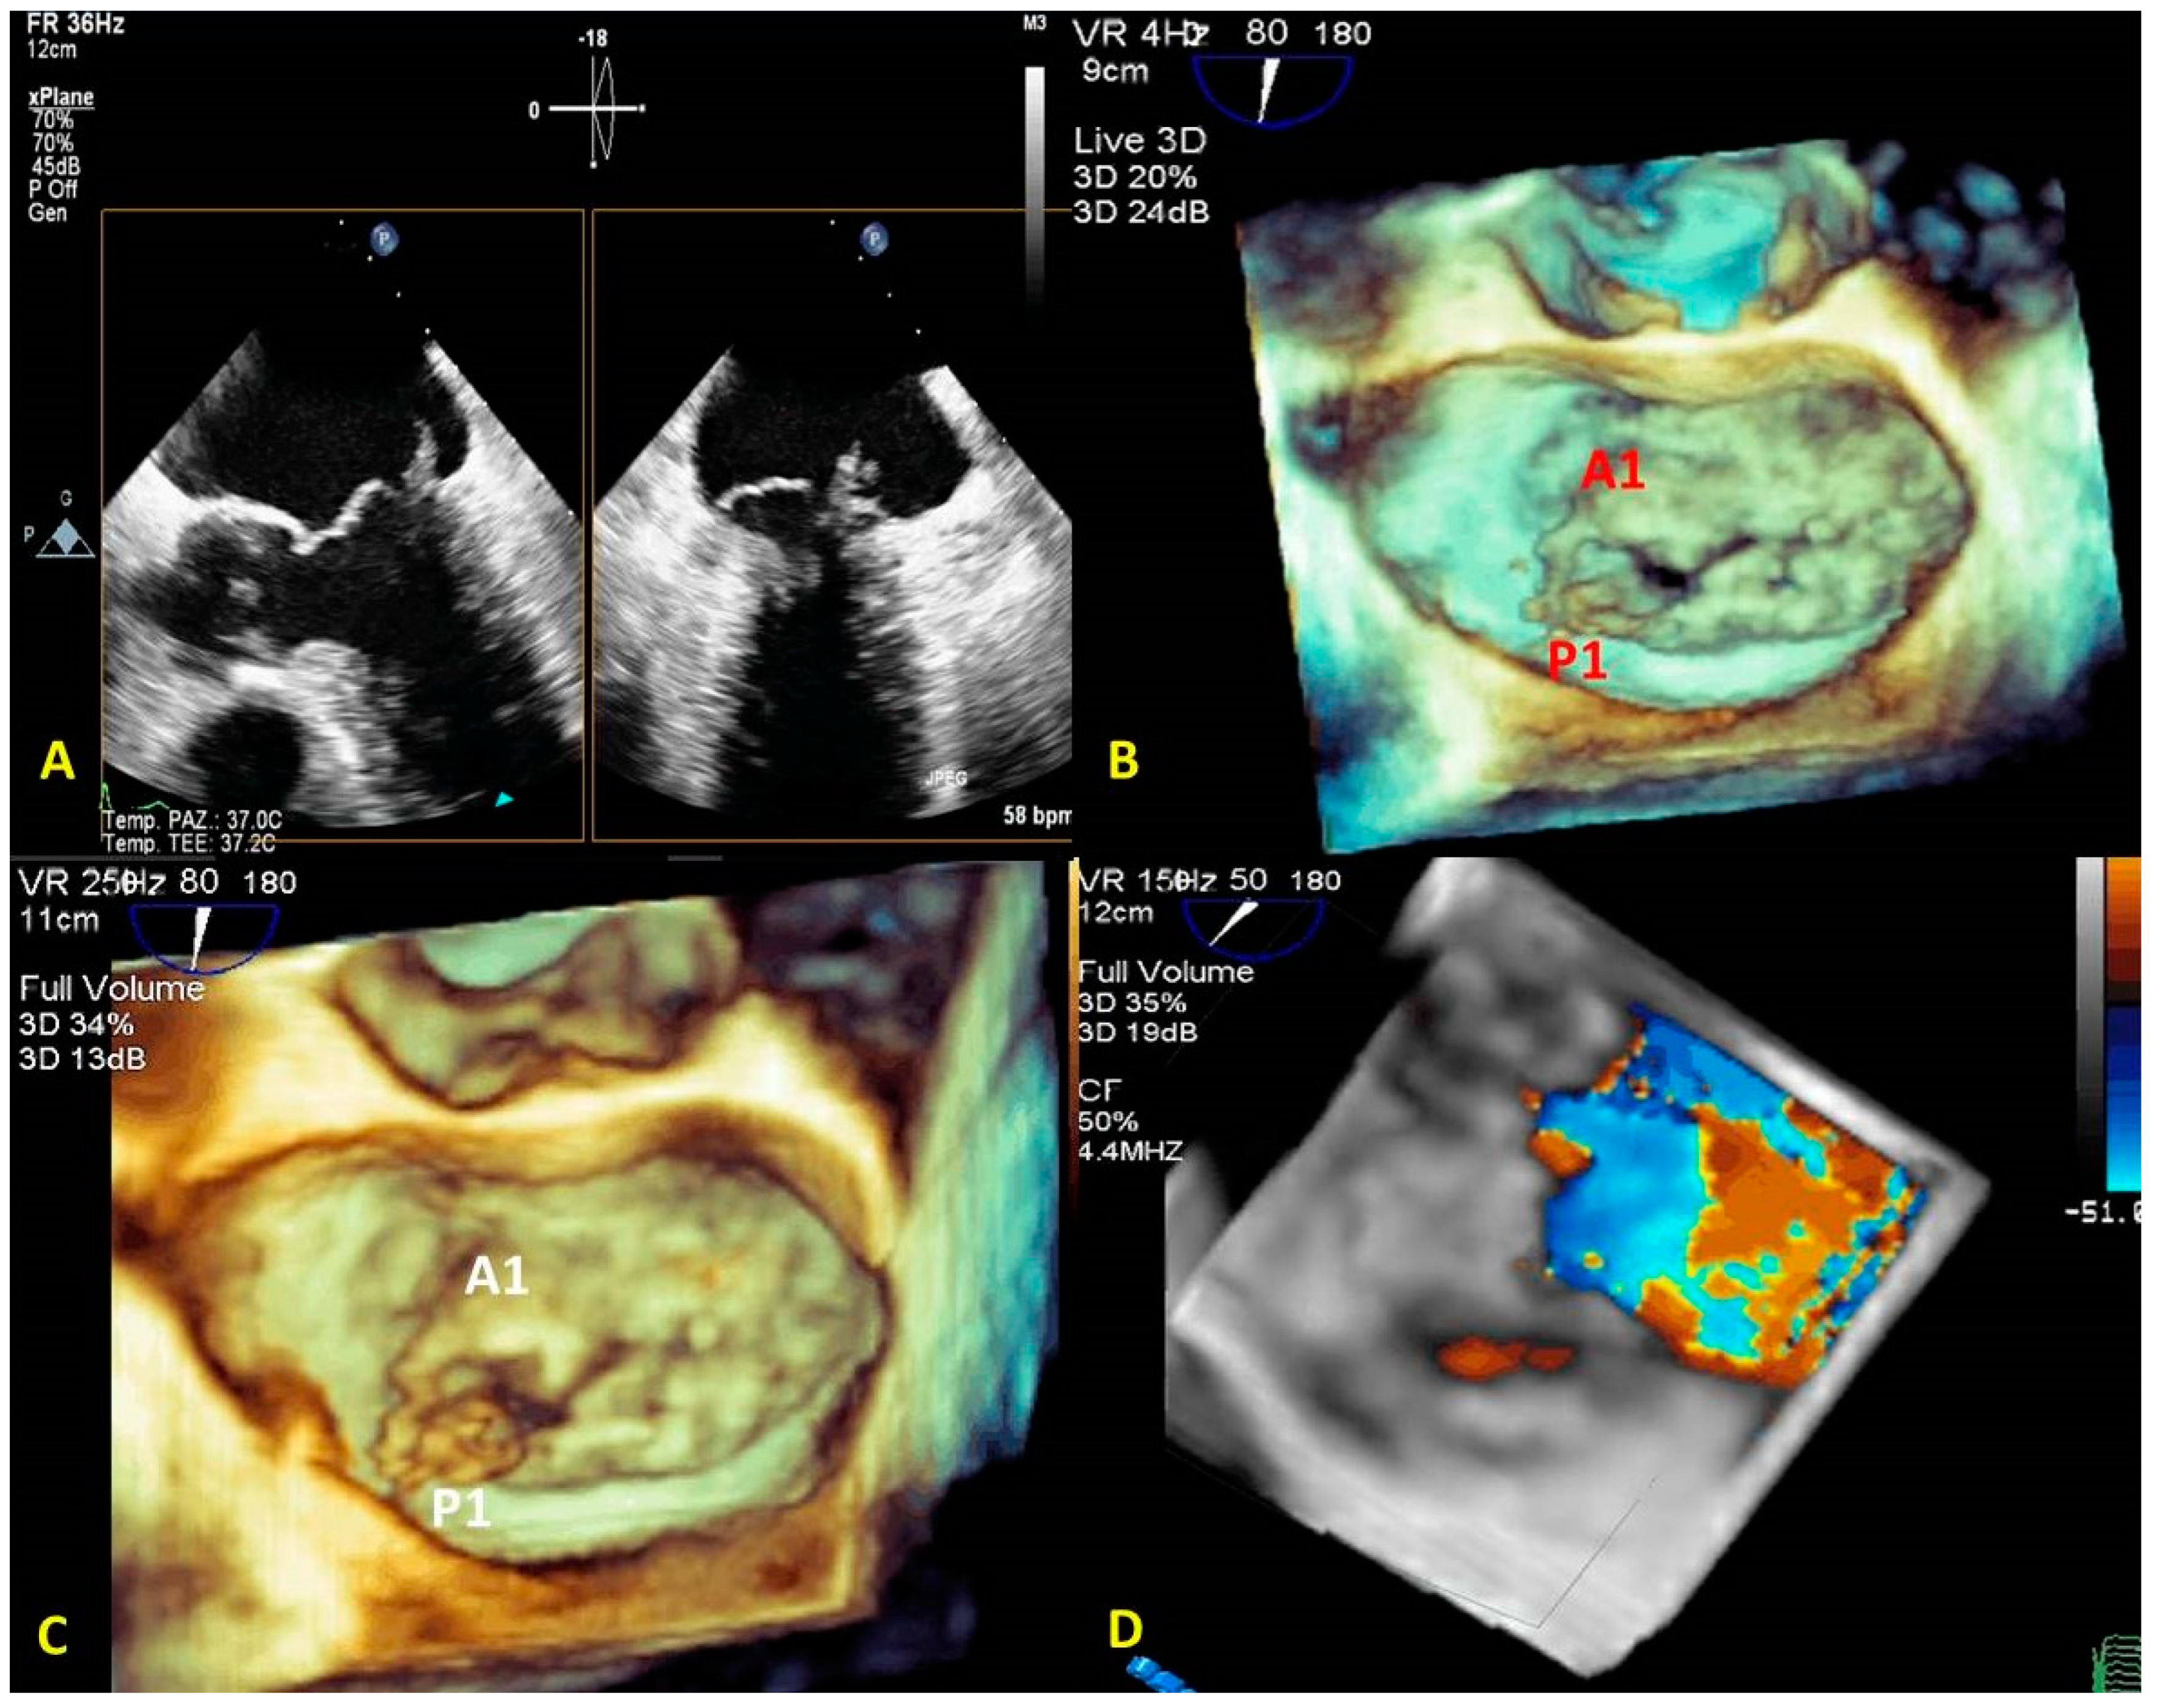

3.1. Anatomical Characterization